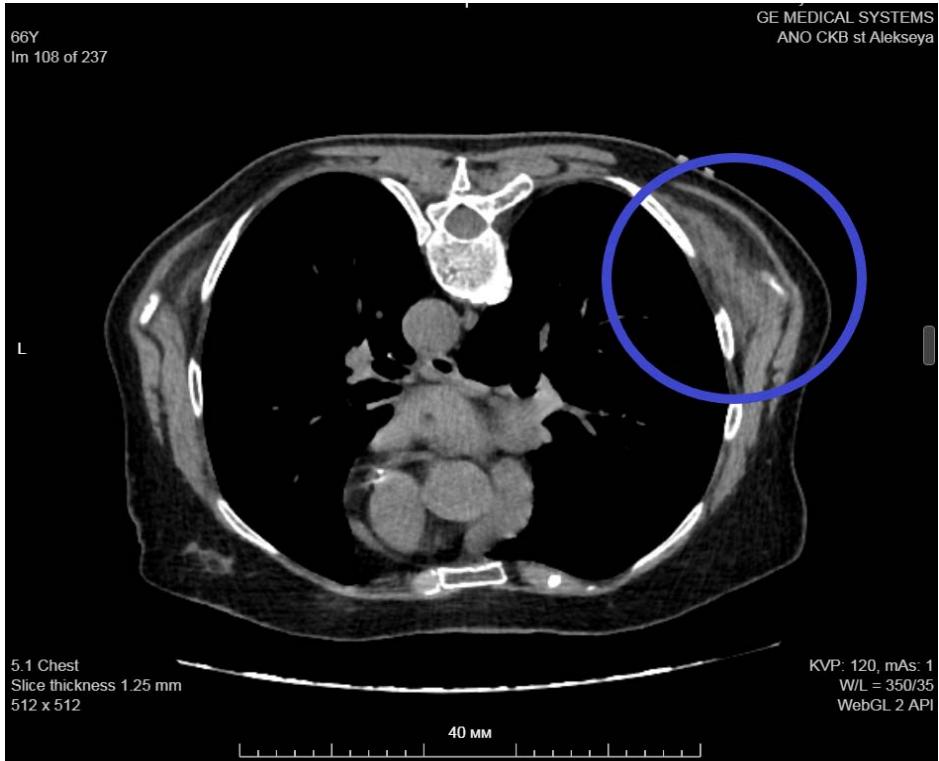

During additional examination, an ultrasound scan (Fig. 7), chest MSCT (Fig. 8) were performed, which showed no evidence for a lipoma, but there was an elastofibroma of the back detected. For differential diagnosis, a biopsy material was taken followed by a histological examination, the obtained results confirmed the diagnosis of "elastofibromadorsi" (Fig. 9).

Figure 8: Chest MSCT. Right elastofibromadorsi: isodense structure with hypodense streaks.

Panel label: a.